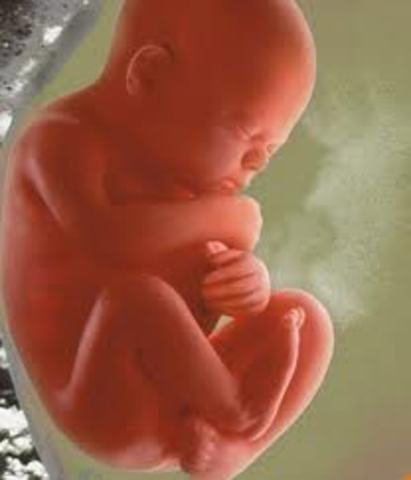

• Month 4 Baby

Month 4 Baby

Size: about 3 inches (7.6 cm) long, 1 ounces (28 g) as month begins.

Can suck it's thumb, sallow, hiccup, and move around.

Facial features become clearer.